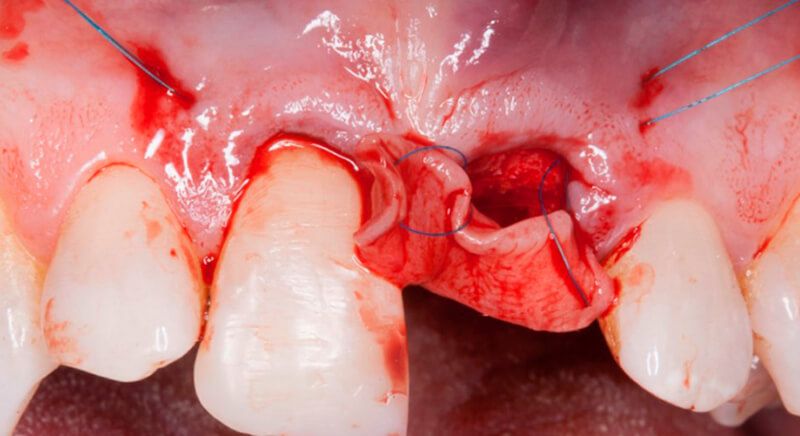

The guided surgery was performed by lifting a full thickness mucoperiosteal flap. A Biomimetic Ocean CC implant, diameter 3.5mm and length 10mm, was inserted using the surgical guide in the ideal three-dimensional position and the defects were regenerated with xenograft and reabsorbable membrane, the nasopalatine duct on the palatine side and the area of dehiscence on the vestibular.

During the same surgical intervention, a short 3mm Avinent healing abutment was positioned and fully covered by the flap. Primary closure was completed and we waited 6 months for the bone graft to mature.